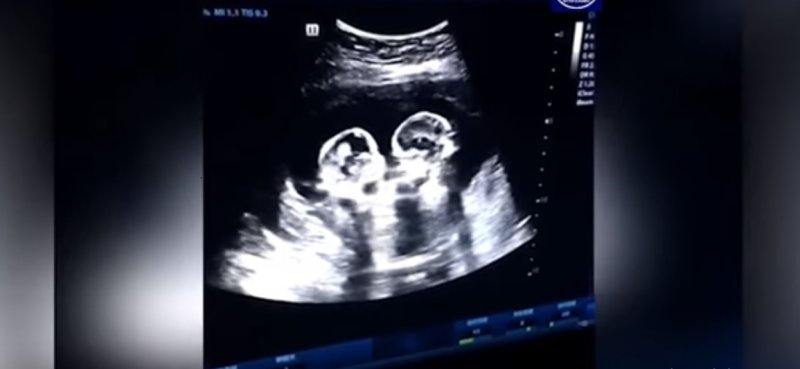

Ababyeyi bo mu Bushinwa baguye mu kantu ubwo bajyaga kwipimisha kwa muganga bafotora abana b’impanga batwite bagasanga bari kurwana.

Ise w’izo mpanga witwa Tao utuye mu mujyi wa Yinchuan, yabwiye itangazamakuru ko mu mpera z’umwaka ushize bafashe amashusho y’abo bana bagasanga basa n’abari kurwana.

Tao avuga ko atari bwo bwa mbere babafata amashusho kwa muganga bagasanga basa nk’abavugana. Mu ntangiriro z’uyu mwaka nabwo basanze bari guhoberana.